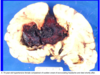

What is this ?

Nontraumatic Intercranial hypertensive hemorhage of the basal ganglia